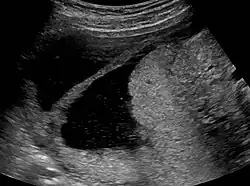

Amniotic sheet on ultrasound

The extent of adhesion formation is critical. Mild to moderate adhesions can usually be treated successfully. Extensive obliteration of the uterine cavity or fallopian tube openings (ostia) and deep endometrial or myometrial trauma may require several surgical interventions and/or hormone therapy or even be uncorrectable. If the uterine cavity is adhesion-free but the ostia remain obliterated, IVF remains an option. If the uterus has been irreparably damaged, surrogacy or adoption may be the only options.

Patients who carry a pregnancy even after treatment of IUA may have an increased risk of having abnormal placentation including placenta accreta[43] where the placenta invades the uterus more deeply, leading to complications in placental separation after delivery. Premature delivery,[37] second-trimester pregnancy loss,[44] and uterine rupture[45] are other reported complications. They may also develop incompetent cervix where the cervix can no longer support the growing weight of the fetus, the pressure causes the placenta to rupture, and the mother goes into premature labour. Cerclage is a surgical stitch that helps support the cervix if needed.[44]